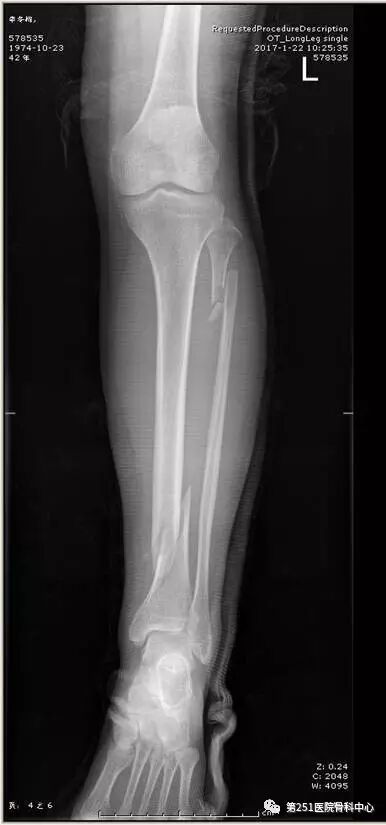

病例2:男性,44岁,车祸伤,双侧胫腓骨骨折(左侧)。